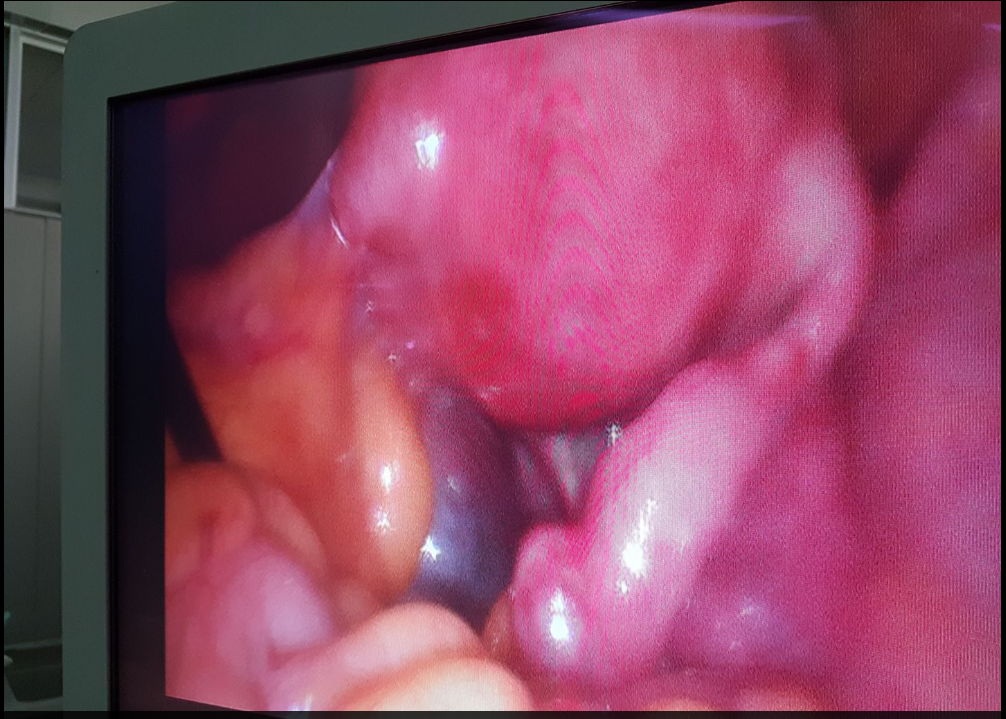

Kistoma Ovari (tumor indung telur)

14 November 2016 pukul 17:44

Dokter Kandungan (OBGYN/Obstetri dan Ginekologi) Cideng Medical Center Cirebon

Kistoma ovarii (tumor indung telur) bener2 penyakit tumor kista yg bisa menyebabkan kemandulan ..seperti pada kasus dibawah ini tampak saluran telurnya ke jepit sampai buntu dan tampak bengkak kebiruan ..jadi gak usah ditunggu lama2 nanti umur keburu bertambah terus dan gak kunjung hamil maka jalan satu2nya ya dilakukan laparascopy kistektomy untuk membuka sumbatannya sehingga diharapkan sel telur dan spermatozoa bisa bertemu lalu terjadilah kehamilan